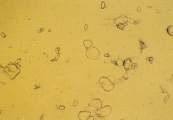

КРИСТАЛЛУРИЯ МОЧЕВОЙ КИСЛОТЫ Особенности Кристаллы мочевой кислоты часто встречаются желтого или желто-коричневого цвета различных форм. Наиболее характерная форма - алмаза или ромбической пластины с концентрическими кругами (рис. 57-61). Также они могут встречаться в виде розеток, состоящих из нескольких агрегированных кристаллов мочевой кислоты. Иногда они встречаются как ромбические пластины с одним или несколькими парными выступами по бокам (рис. 62-63). Гораздо реже они встречаются в форме шестигранных кристаллов, напоминая цистин. Однако, шестигранные кристаллы всегда встречаются вместе с типичными кристаллами алмазной или ромбовидной формы. Кристаллы мочевой кислоты растворимы в гидроксиде натрия, но нерастворимы в спирте, соляной кислоте и уксусной кислоте. Интерпретация Являясь довольно распространенной среди людей, кристаллурия мочевой кислоты нечасто встречается у собак и кошек. Кристаллы мочевой кислоты формируются после добавления 10% уксусной кислоты в мочевой осадок собак и кошек, содержащий аморфные кристаллы мочевой кислоты и аммония урата. Также могут формироваться кристаллы натрия урата. Необходима выдержка 20-30 мин. для уксусной кислоты чтобы кристаллы стали видимыми. Если оставить их на ночь с влажной губкой в чашке Петри, то они могут выпасти. Рис. 57. Микрофотография кристаллов мочевой кислоты в мочевом осадке 4-летнего кастрированного самца енота (не окрашено, увеличение Х 25). Рис. 58. Микрофотография кристаллов мочевой кислоты в мочевом осадке собаки, описанной в рис.44. Эти кристаллы были образованы путем добавления 10% уксусной кислоты к мочевому осадку, содержащему кристаллы аммония урата (не окрашено, увеличение Х 52). Рис. 59. Микрофотография слоистого кристалла в мочевом осадке собаки, описанной в рис. 49. Его появление свидетельствует об активном росте кристалла (не окрашено, увеличение Х 128). Рис. 60. Микрофотография кристаллов мочевой кислоты в закисленном мочевом осадке собаки, описанной в рис 43. (не окрашено, увеличение Х 128). Рис. 61. Сканированная электронная микрофотография кристалла мочевой кислоты алмазной формы в закисленном мочевом осадке собаки, описанной в рис. 43 (увеличение Х 2,340). Рис. 62. Микрофотография кристаллов мочевой кислоты в закисленном мочевом осадке 3-летнего самца далматина (не окрашено, увеличение Х 51). Рис. 63. Сканированная электронная микрофотография различных форм кристаллов мочевой кислоты в закисленном мочевом осадке собаки, описанной в рис.49 (увеличение Х 792).